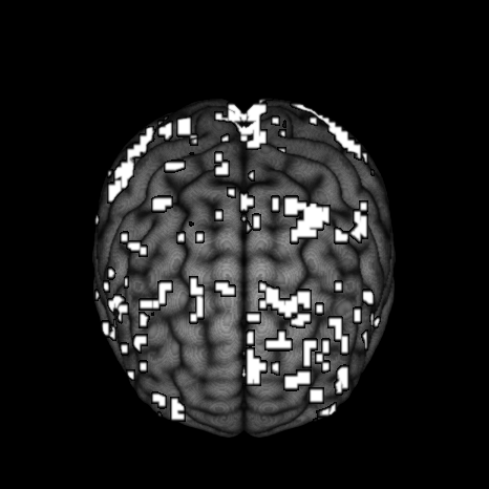

Our motivating example comes from a single subject in a fMRI experiment examining a face-repetition stimulus. The experiment involves the presentation of either famous faces (F) or non-famous faces (N) with each type of face presented two times. Convolving this experiment design with the canonical hemodynamic response function and its time and dispersion derivatives leads to a design matrix with twelve columns plus one extra column for an intercept term in the regression model. After performing the necessary pre-processing steps as described in Penny et al. (2005), we fit a simple linear regression at each of the voxels. After obtaining the residuals from each voxel-specific fit, we fit an AR process up to order for each voxel using the “ar” function in R. We then selected the optimal AR orders based on the AIC criterion. Figure 1 displays a pictoral representation of the results.

Figure 1 shows considerable variablity in the estimated AR order across voxels. While most of the estimated optimal AR orders are 4 or less, higher orders up to are selected at some of the voxels. Furthermore, these estimated AR orders tend to show some extent of spatial clustering. If, as is often done, we simply model the data using a homogeneous low-order AR process, then the voxels with higher order estimated AR orders would be incorrectly modeled, and this inaccuracy in the modeling of temporal noise will have an impact on the inference on the covariates of interest (via underestimated standard errors), resulting in potentially false inferences about brain activation. To address this issue, we propose a spatially varying autoregressive order (SVARO) model, where the AR orders vary spatially across the brain. This is made possible by adopting a spike-and-slab prior with a stochastic search variable selection scheme. Spatial clustering of AR orders is incorporated by imposing an Ising prior (Ising, 1925) as the latent indicator for the spike and slab prior. We update the latent indicators using the Swendsen-Wang algorithm (Swendsen and Wang, 1987) alternating with Gibbs sampling in our MCMC algorithm. To prevent the phase transition problem associated with the Ising model, we derive theoretical bounds as in Li et al. (2015) and use these bounds to prevent critical slowing of the algorithm. We compare our model with the GLM-AR model of Penny et al. (2007) (implemented under two schemes: our self written MCMC sampler and the VB algorithm available in the SPM software) in terms of mean squared error (MSE) and sensitivity. We conduct these comparisons using two simulation studies and then compare results on the motivating data set.